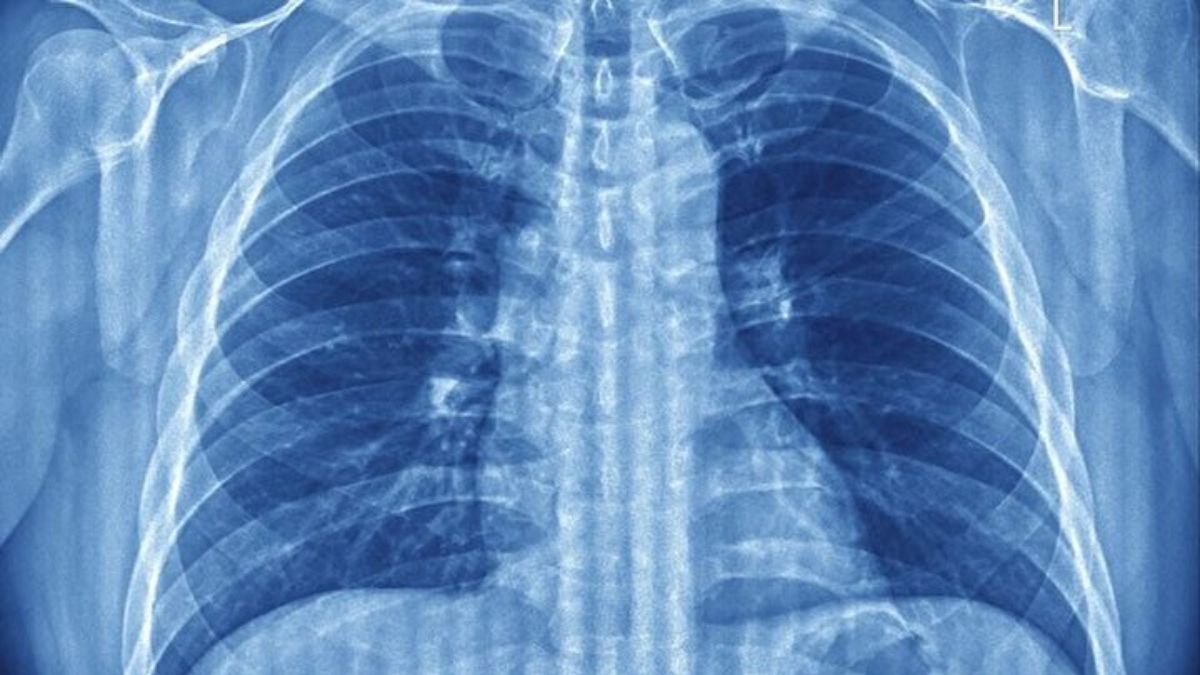

Medicina.az xəbər verir ki, ABŞ-da yerləşən tədqiqat qrupu dərin nəfəsin ağciyərlərin çökməsinin qarşısını alan və alveol adlanan hava kisələrini qoruyan təbii bir hərəkət olduğunu ortaya qoyub.

“Science Advances” jurnalında dərc edilən bir araşdırma, siçanlar üzərində aparılan təcrübələrdə ah çəkmənin ağciyərlərdə səthi gərginliyi azaldan maddəni yenidən aktivləşdirdiyini müəyyən edib.

Bu maddə hər nəfəsdə hava kisələrinin çökməsinin qarşısını alır, oksigen mübadiləsini təmin edir.

Tədqiqatçıların fikrincə, bu refleksin əsas məqsədi ağciyər səthinin quruması və yapışmasının qarşısını almaqdır.

Xüsusilə uzun müddət hərəkətsizlik və ya tənəffüs xəstəlikləri zamanı bu rəqəm azaldıqda ağciyər funksiyasının zəiflədiyi bildirilir.